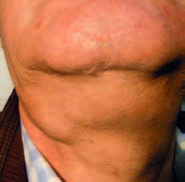

Se presentan unas imágenes de un paciente varón de 55 años, sin alergias conocidas, exfumador desde hace unos pocos años, que consulta por urgencias por inflamación brusca submandibular derecha dolorosa, tiene antecedentes de 5 episodios de submaxilitis derecha por cálculo salivar, desde hace 5 años. En la exploración de la salida sublingual del conducto de Warton se aprecia salida de saliva con supuración. Después de tratamiento antibiótico durante una semana, mejora la inflamación, saliendo saliva clara normal, quedando una hipertrofia de la glándula (figura 4).